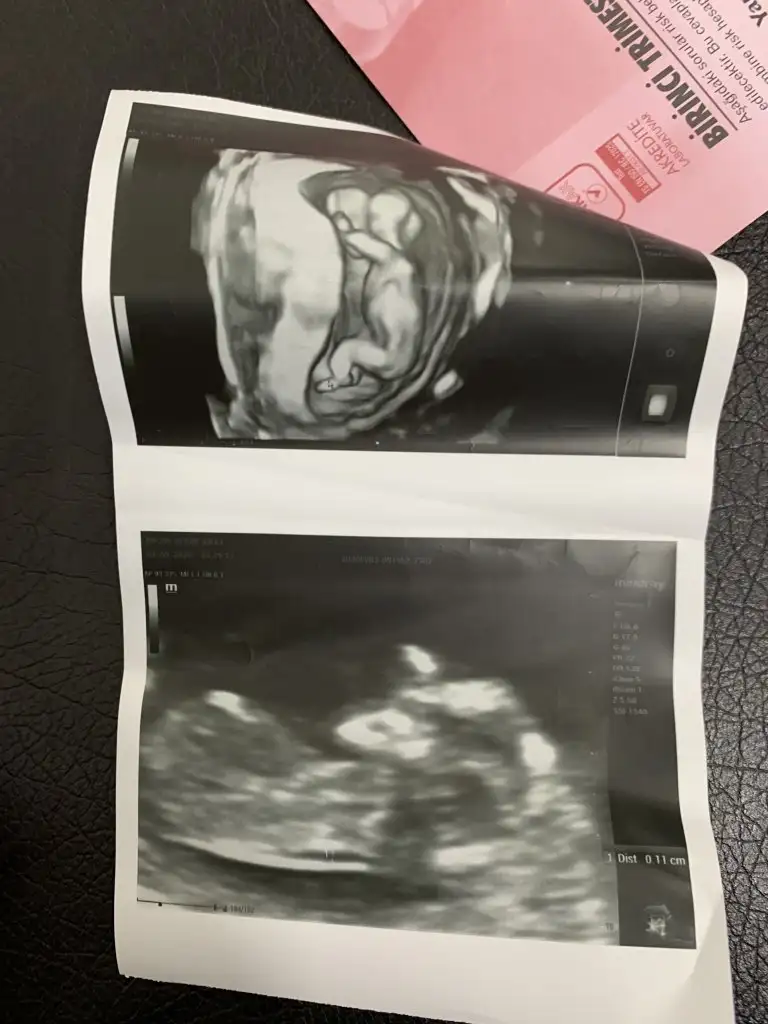

Buda benim bebişim 12 haftalık cinsiyeti sizce nedir😊

45CFB82A-2675-4DCE-89D8-BF5501063824.webp

0B18C297-463A-428C-B895-F773D8C07173.webp